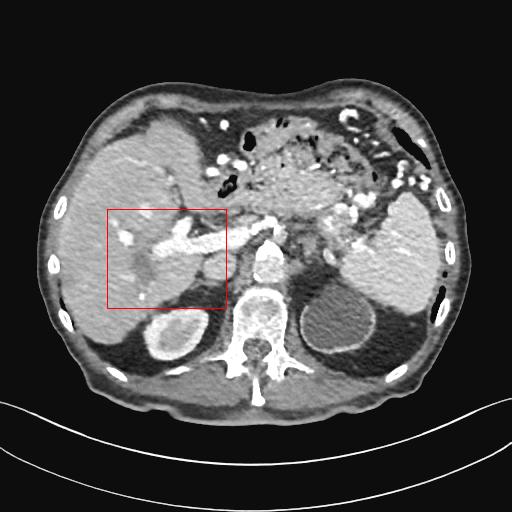

Figure 3: Comparison of denoising performance of different network. The boundary line of different organ extracted from the NDCT image is superimposed on other images. As seen, many pixels are missing around the boundary line in the output of M1

Figure 4: Zoomed version of the ROI taken from the images of Figure 3. In the zoomed version missing boundary pixel is clearly visible in the output of M1.

This section systemically investigates the efficacy of every module proposed in this study. We considered three different networks; first, baseline model(M1), where the inverting block is replaced with dense block, and trained using minimizing mean square distance between two noisy observations(i.e. fsubscript𝑓\mathcal{L}_{f}). Next, two independent baseline model(one for forward mapping, one for reverse mapping) is jointly trained using a linear combination fsubscript𝑓\mathcal{L}_{f}, and rsubscript𝑟\mathcal{L}_{r}, similar to cycle consistent network paradigm. The forward mapping network is used for testing. We refer this model as M2. In both M1, and M2, we increased the depth of the network to make the representation power of these networks comparable with inverting network. Finally, the proposed method, referred as M3. Table 2 depicts the objective evaluation of the three networks using the D1 dataset. Both M2 and M3 use reverse mapping to regularize the network; the influence of the same in the denoising performance is evident from Table 2. Adding cycle consistency loss has improved the performance of the same baseline model significantly. The inverting network performed considerably better than the network M2. It improves PSNR by 0.23dB. As discussed in the above section, in case cycle consistency loss, an additional network is trained, but that does not always guarantee invertibility, whereas inverting network architecture inherently possesses reversibility, which acts as a strong regularizer. In Figure 3 we have shown denoising performance of different networks visually. To demonstrate the requirement of regularization, we first extract the boundary line of the various organ from the NDCT image and superimpose the boundary line on the output of different networks. As shown in Figure 3, many pixels around the boundary line of M1 network output are missing. Using the reverse mapping, the issue of the end-organ missing pixel is successfully overcome in M2 and M3. The granular pattern is also less present in the M3 than M2. The zoomed version of a ROI taken from the images of Figure 3 is given in Figure 4 for better perception. In Figure 5 we give an example of the performance of the invertible network in reverse mapping. Here, the predicted LDCT image is produced by using the predicted clean image of the forward mapping as the input for reverse mapping. As shown, the predicted noisy pattern is similar to the original noise pattern. The same streaking artifacts are present in both the noise pattern; also, the noise variance is different in the various spatial region depending on the signal intensity of the original CT image. It validates that the loss of information in reverse mapping is minimal. Due to the invertible network’s structural advantage, the network also preserves every information present in the input image in the forward mapping.